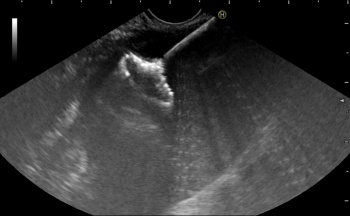

Эндоскопическая гастроцистостомия с применением эндосонографической навигации и установкой саморасправляющегося стента имеющего форму «гантели» выполнена 42-летнему пациенту. При обследовании у мужчины выявлена киста поджелудочной железы диаметром 7 см.

Трансмуральное дренирование – во время осмотра желудка и ДПК визуализируется выпячивание стенки органа соответствующее проекции псевдокисты. В этом месте делают прокол, создают сообщение между полостью кисты и просветом желудка, устанавливают стент.

- Псевдокиста тела поджелудочной железы опорожнилась в просвет желудка через сформированное при помощи эндопротеза соустья. Содержимое кисты аспирировано из желудка. Под эндоскопическим и рентгенологическим контролем определены позиция и степень раскрытия саморасправляющегося стента, выполнен осмотр и санация полости псевдокисты, - делится Александр Леонидович Кострубин, заведующий эндоскопическим отделением СОКБ.

Оперативное вмешательство врачи проводят под тройным контролем –рентгенологическим, эндоскопическим и эндосонографическим. Сочетание этих методик обеспечивает пациентам минимальные риски и максимальную эффективность оперативного вмешательства.